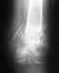

Re: Переломы костей голени

это рентгенограмма через 3 месяца после операции